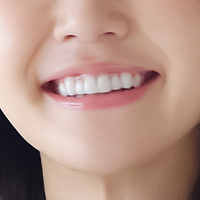

初診時

現在